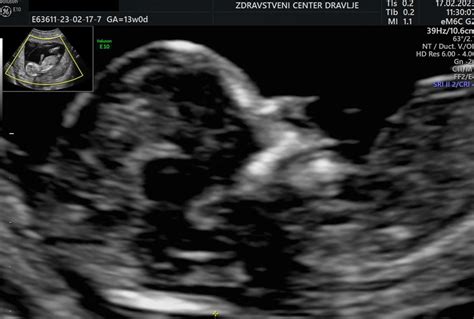

Merjenje nuhalne svetline se izvaja v obdobju med 11. in 14. tednom nosečnosti, natančneje, ko je dolžina ploda od temena do trtice med 45 in 84 mm. Ta časovni okvir je ključen, saj se v tem obdobju tekočina v zatilju ploda najbolj zanesljivo meri. Preiskava se opravi ultrazvočno skozi trebušno steno (transabdominalno), le v redkih primerih, ko je vidljivost slaba, se uporabi vaginalna sonda (transvaginalni ultrazvok). Pred preiskavo je priporočljivo, da ima nosečnica izpraznjen sečni mehur, kar izboljša kvaliteto slike.

Med samo preiskavo ultrazvočno ocenimo več parametrov. Poleg meritve debeline nuhalne svetline, ki je prostor med kožo in mehkimi tkivi, ki pokrivajo hrbtenico ploda, preverimo še: